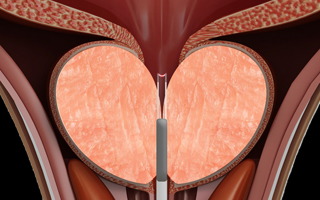

02

2단계

플라즈마를 활성화 상태로 후방으로 이동하고, 비활성화 상태로 전방으로 이동하며 조직을 제거 합니다.